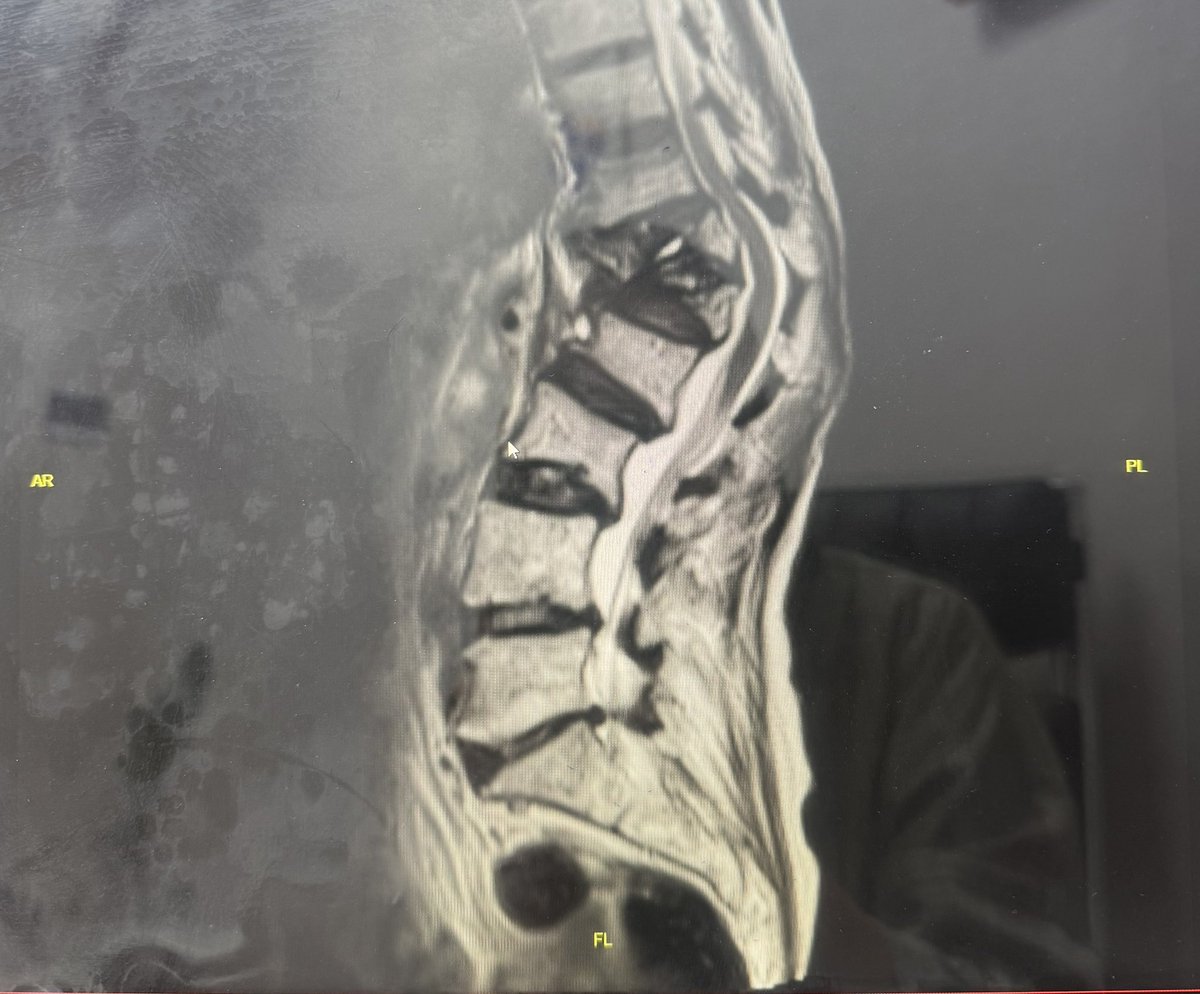

من یک پزشکم

سوگند خوردهام انسانها را درمان کنم و حافظ اسرارشون باشم

اگر نیاز به مشورت پزشکی داشتید، به من پیام بدید

🇮🇷 پزشک / بیماریهای ستونفقرات / عضو انجمن پی و مهره ایران / #بدون_سهمیه کارشناس ارشد جامعهشناسی - INFP-A - بنیانگذار #کافیگپ @CoffeeGap_ 🇮🇷